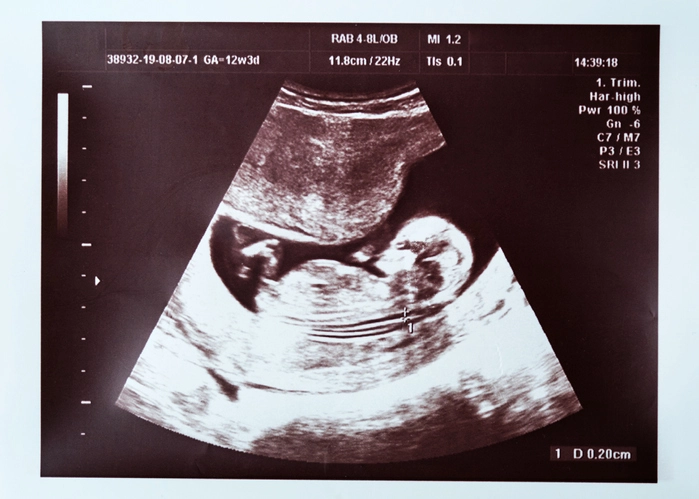

مدار الساعة - انتشرت أخبار عن حالة نادرة لامرأة لديها طفل ينمو في كبِدها بعد أن شارك أطباء تفاصيل الحالة على موقع تيك توك.

لكن المفاجأة جاءت عندما تبين أن "ما وجدوه في كبد المريضة هو طفل لقد كان لديها حمل خارج الرحم، في كبدها".

وأضاف الدكتور نارفي: "نرى حالات الحمل خارج الرحم [الحمل المنتبذ] أحياناً في البطن، لكن لا نشهدها أبداً في الكبد. هذه هي الحالة الأولى من نوعها بالنسبة إليَّ".

كما شارك الدكتور كاران راج، وهو طبيب آخر لديه حساب على الموقع و236 مليون متابع، تاريخ الحالة أيضاً، وقال راج: "إنها إحدى أكثر فحوصات التصوير المقطعي التي رأيتها إثارةً لخوفي، فهي امرأة تبلغ من العمر 27 عاماً، ولديها جنين سليم عمره أسبوعان ينمو في الفص الأيمن من كبدها".

وأشار الدكتور راج إلى أن ما يسمى الحمل المبدي خارج الرحم حالة شديدة الندرة، حتى إنه "لا يوجد سوى عدد قليل من الحالات الموثقة في مراجع الطب كلها"، وأضاف أن "الكبد عضو ترتبط بنيته بالعديد من الأوعية الدموية، لذا فإن أي قوة ضاغطة عليه يمكن أن تؤدي إلى نزيف داخلي حاد".